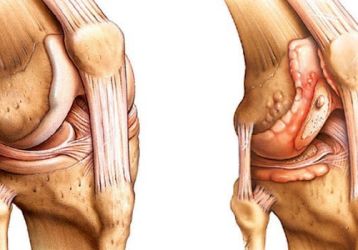

Чем отличается артрит от артроза коленного сустава: анализ признаков болезней

Методы диагностики и сравнение основных симптомов и признаков артрита и артроза коленного сустава, особенности обоих заболеваний.